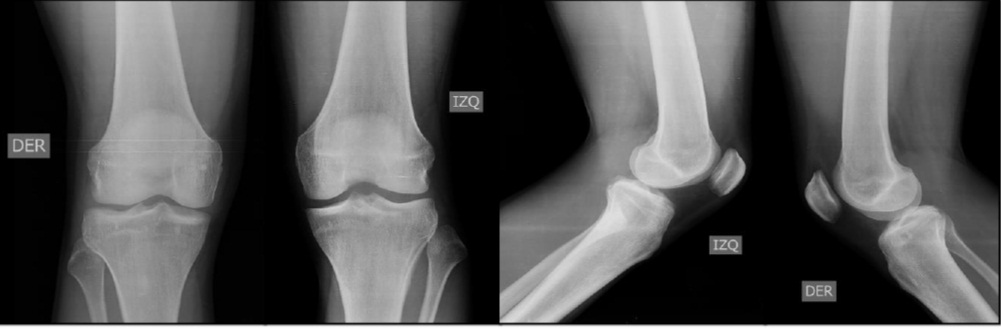

Luxación traumática aguda de la articulación tibioperonea proximal. Reporte de un caso y revisión bibliográfica. [Acute traumatic dislocation of the proximal tibiofibular joint: case report and review of the literature].